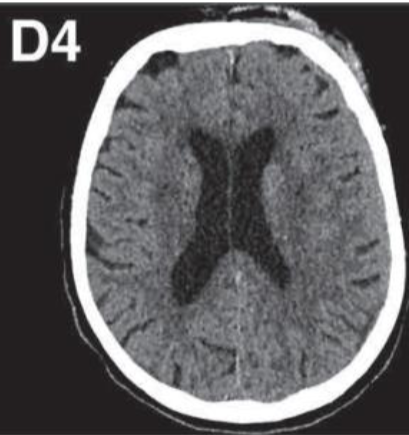

overall decrease in gross brain weight due to:

decreased volume of white matter

atrophy of the corpus callosum

compensatory dilation of the lateral ventricles